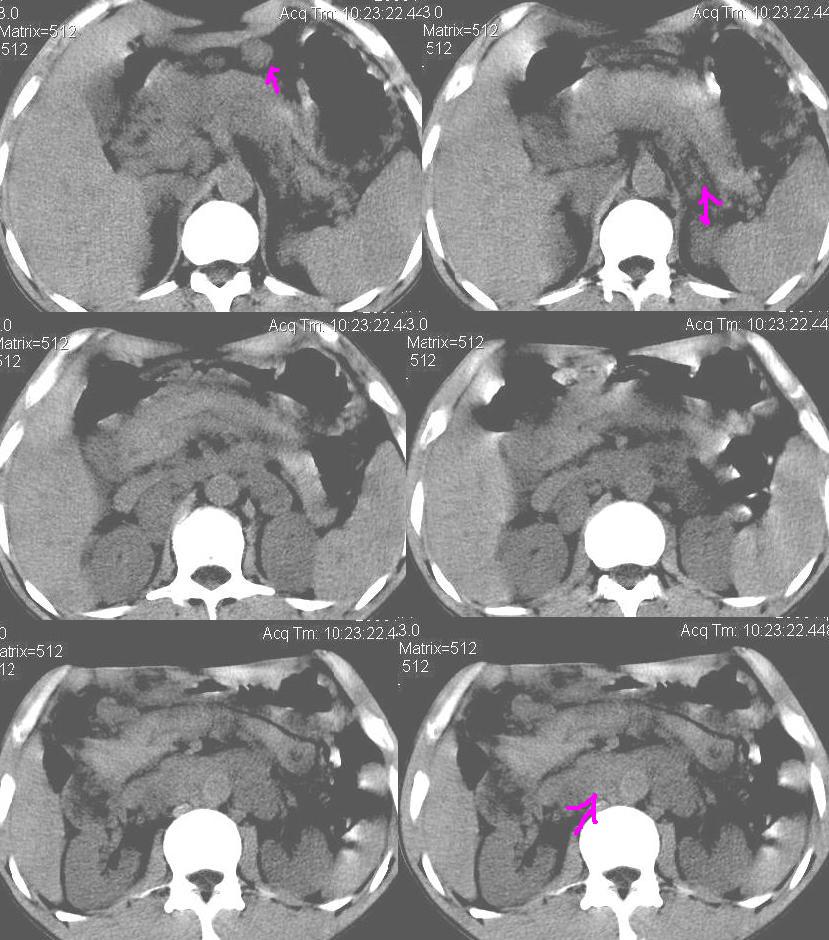

上腹部疼痛一月,呕吐10天,发现左侧颈部包快10天 胸部cr片未见明显异常。

腹膜后淋巴结增大,转移、淋巴瘤?胰腺增大,胰腺炎?占位?颈部考虑增大淋巴结。建议腹部增强扫描。

缺少强化资料,暂考虑胰腺癌广泛转移.

黑!广泛淋巴结肿大不符合胰腺癌转移。胰腺周围淋巴结肿大致使胰腺看起来大。考虑淋巴瘤可能大。

颈部及腹膜后淋巴瘤可能性大